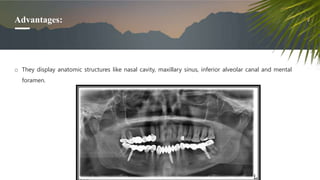

Advantages:

o They display anatomic structures like nasal cavity, maxillary sinus, inferior alveolar canal and mental

foramen.